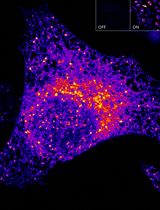

Stimulation of G protein-coupled receptors (GPCR) by hormones and neurotransmitters elicits cellular responses, many of which result from alterations in the concentrations of cytosolic cAMP and Ca2+. Here, we describe a microplate reader fluorescence resonance energy transfer (FRET) assay that uses the genetically encoded biosensors H188 and YC3.60 so that it is possible to monitor the kinetics with which alterations of [cAMP] or [Ca2+] occur in monolayers or suspensions of living cells exposed to GPCR agonists. This protocol uses HEK293 cell lines doubly transfected with a FRET biosensor and a recombinant GPCR of interest (e.g., glucagon receptors, CCK2 receptors, or NPY2R receptors). The protocol allows for rapid screening of small molecule GPCR agonists and antagonists, and it is also useful for discovery of synthetic mono-, dual-, and tri- agonist peptides with GPCR activating properties.

Live-cell fluorescence resonance energy transfer (FRET) assays in combination with microscopy and digital imaging technologies are commonly used to monitor the kinetics with which levels of cAMP and Ca2+ fluctuate in response to GPCR agonist stimulation. Here, we report an alternative approach that does not use microscopy but that instead enables FRET-based detection of cAMP and Ca2+ in a 96-well format using an automated microspectrofluorimeter and monolayers or suspensions of living cells. The protocol uses genetically encoded biosensors so that averaged kinetic data for pharmacological studies can be obtained in real time using a microplate reader under conditions in which GPCR agonists are applied at known concentrations. These FRET assays use cell lines stably expressing the cAMP biosensor H188 (Klarenbeek et al., 2015) or the Ca2+ biosensor YC3.60 (Nagai et al., 2004), both of which exhibit superior dynamic range in comparison to earlier FRET reporters. Our protocol describes how H188 or YC3.60 can be expressed stably with recombinant GPCRs so that precise dose-response analysis is achievable. This protocol builds on our published studies, whereby novel dual agonist and triagonist properties of synthetic GPCR agonist peptides (e.g., EP45 and GGP817) were discovered (Chepurny et al., 2018 and 2019).

Using the genetically encoded biosensor Epac1-camps (Nikolaev et al., 2004), we were the first to develop a 96-well microplate FRET assay in which fluctuations of [cAMP] were monitored in monolayers of living cells in real time using a microspectrofluorimeter (FlexStation 3, Molecular Devices) (Chepurny et al., 2009). More recently, we have optimized this approach for purposes of drug discovery in a high-throughput mode. The major technical advance concerns our use of H188 and YC3.60, both of which we find to be highly responsive to cAMP and Ca2+, respectively. Importantly, our plate reader FRET assays using H188 or YC3.60 require their high-level expression, either by stable transfection to generate clonal cell lines (Chepurny et al., 2018), or by adenoviral transduction of cell lines (Chepurny et al., 2018 and 2019). Transient transfection is not useful since low-level expression of these biosensors is not compatible with the limited light detection limits of available microplate readers.

For the H188 reporter expressed in our clonal C24 HEK293 cell line, the cAMP-elevating agent forskolin induces a maximal 100% increase of the 485/535 ∆FRET ratio, a response that greatly exceeds the 12% value typically observed using Epac1-camps (Chepurny et al., 2009 and 2018). This C24 clone exhibits high sensitivity (EC50 500 nM) and excellent Z-score (0.77) when testing forskolin (Chepurny et al., 2018). Calibration of the FRET signal is obtained in assays that use digitonin-permeabilized C24 cells expressing H188 and that are bathed in known concentrations of cAMP (Chepurny et al., 2018). When administering forskolin by its bolus injection into individual wells of a microplate containing monolayers of C24 cells, the time course of adenylyl cyclase activation and resultant cAMP production is monitored with high precision within the first 30 s.

Our real-time kinetic assay using H188 and living cells differs from single-endpoint HTR-FRET assays that monitor levels of cAMP in cell lysates. For example, the LANCE® cAMP assay (Perkin Elmer) uses a Europium-labeled cAMP tracer (FRET donor) in combination with a fluorophore-tagged anti-cAMP antibody (FRET acceptor), both of which are added to a reaction mixture so that the competition of fluorescent cAMP and non-fluorescent cAMP (i.e., endogenous cAMP) for the anti-cAMP binding site on the antibody can be measured. In contrast, H188 is unimolecular in which the cAMP-binding protein Epac1 is flanked by the FRET donor mTurquoise2∆ and the FRET acceptor cp173 Venus-Venus so that a decrease of FRET occurs upon binding cAMP (Klarenbeek et al., 2015). YC3.60 instead uses a Ca2+-binding domain of calmodulin (CaM), and the CaM-binding peptide M13, in combination with the FRET donor ECFP∆11, and the FRET acceptor cp173Venus so that an increase of FRET occurs upon binding Ca2+ (Nagai et al., 2004). Unlike HTR-FRET assays, H188 and YC3.60 allow live-cell real-time determinations of FRET in the kinetic mode.